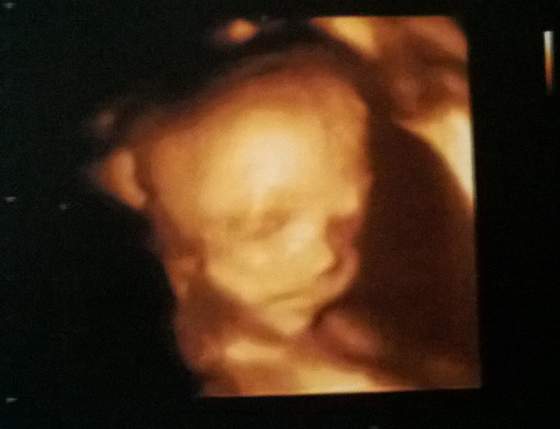

21+3 - taki obrażony :-p